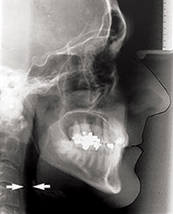

Figure 1: Lateral cephalometric radiographs showing the posterior

airway space before (top) and after MMA (bottom).

It has become increasingly recognised that carrying out mandibular and maxillary osteotomies can also have a profound positive or negative effect on the posterior airway space at both the level of the tongue base and the palate, which is predictable and dependent on the direction of movement. By advancing the mandible and the maxilla 8-10mm especially in combination with an advancement genioplasty the posterior airway space can be greatly improved. This has been measured on lateral cephalometric radiographs and more recently 3D computerised tomography (CT) has demonstrated the increased airway volume achieved [6]. More importantly than radiographic appearance, however, is the resolution in symptoms of OSA and demonstrable improvement in polysomnography studies. It is becoming increasingly recognised that orthognathic mandibular setback surgery can lead to conversion into OSA [7].